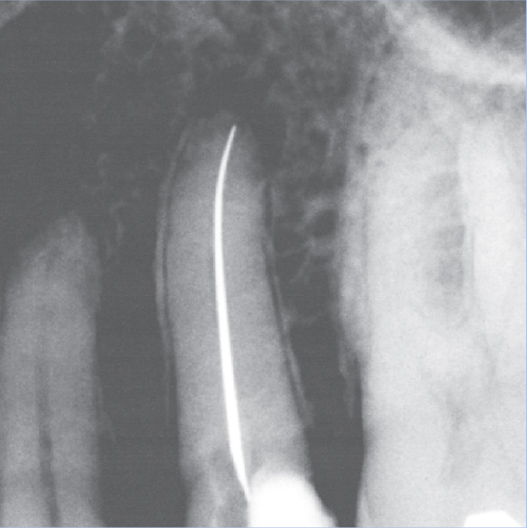

After

After Root Canal treatment